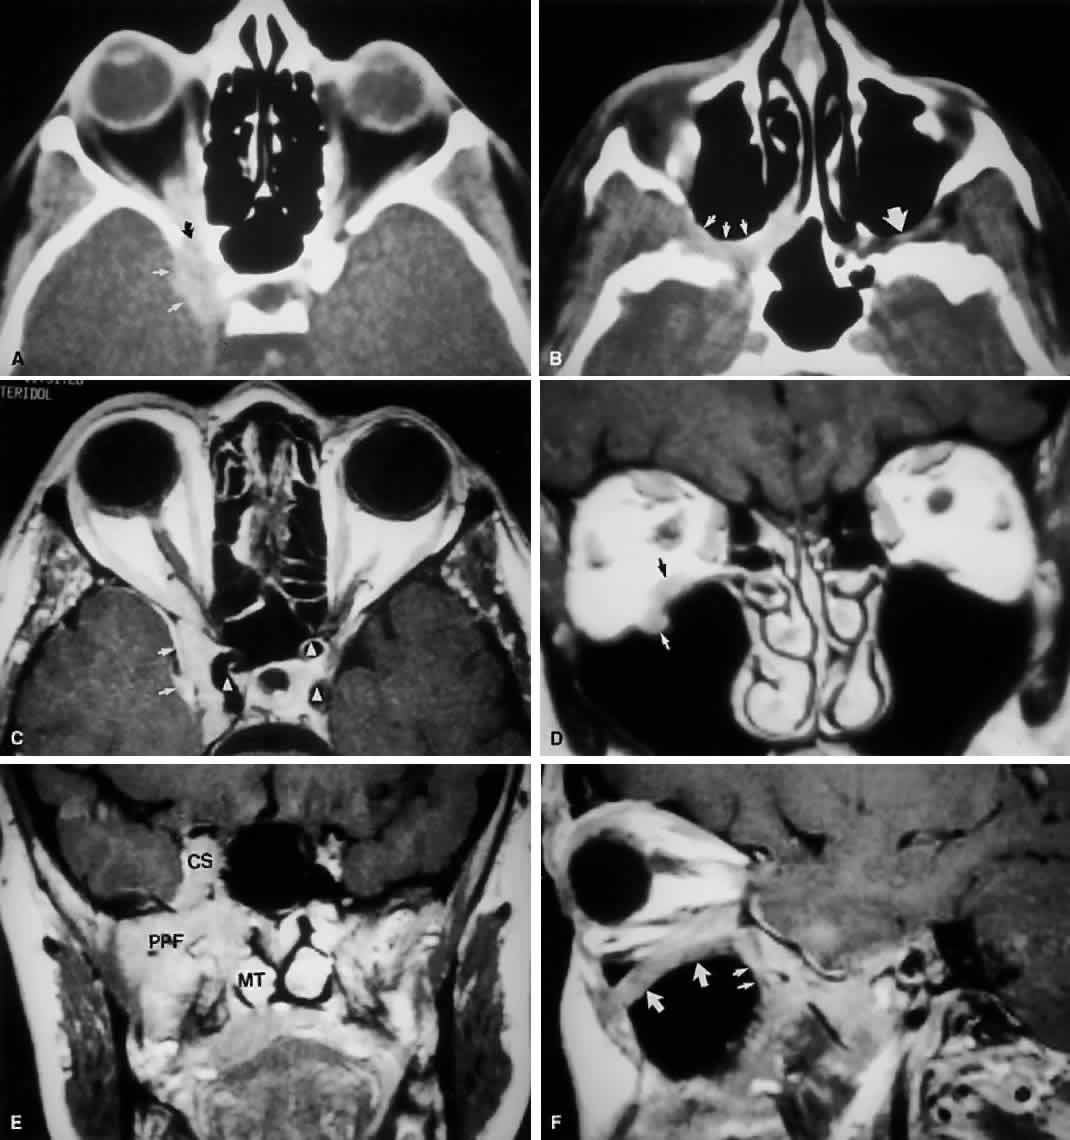

Radiographically, the spaces and foramina of the orbital apex may be considered to lie in three tiers (Fig. 8). The CS is found on the same level as the orbital apex, connecting directly with it via the superior orbital fissure (SOF) to form the middle tier. The inferior tier is formed by the inferior orbital fissure (IOF), which provides direct communication between the orbital apex and the pterygopalatine fossa, a vertically oriented space directly behind the maxillary sinus. Finally, the optic canal has no direct communication with any of the aforementioned spaces and should be considered to lie above the SOF and CS, exiting the orbit in a superomedial course through the body of the sphenoid as the superior tier.26 Orbital apical lesions can therefore gain ready access to the CS and pterygopalatine fossa (Fig. 9). Spread into the cranial vault through the optic canal is usually limited to lesions of the optic nerve (glioma) or nerve sheath (meningioma).

Fig. 8. Coronal CT image (bone window) of the orbital apex in a patient with facial trauma. Note the position of the posterior orbital foramina. The optic canal (A) is always seen in conjunction with the laterally adjacent anterior clinoid process (B) on both axial and coronal views. Slightly lower, the superior orbital fissure (C) communicates with the CS, found directly behind it. The inferior orbital fissure (D) provides communication through the orbital floor with the pterygopalatine fossa.

Fig. 9. An orbital lymphoma involving the skull base provides accentuation of the apical spaces of the orbit. A. On this axial CT, the lesion infiltrates the CS, causing bulging and local invasion of its lateral dural wall (small arrows). Invasion into the orbital apex through the superior orbital fissure (curved arrow) is seen. Note that the patient is slightly rotated in the scanner, because the anterior clinoid and optic canal are visualized on the uninvolved side. B. More inferiorly, the mass has invaded the pterygopalatine fossa (small arrows), located just posterior to the maxillary sinus. On the uninvolved side (large arrow), the fossa has areas of radiolucency, indicating the fat that normally occupies this space. C. Axial MRI, T1-weighted image with gadolinium but without fat suppression. The carotid siphon is seen within each CS as a flow void (arrowheads). Once again, note the inflamed lateral dural wall of the CS and local invasion of the brain parenchyma (small arrows).D. Coronal T1-weighted MR image. The inferior rectus muscle is labeled with a black arrow. The lymphoma has infiltrated the infraorbital canal (white arrow) within the orbital floor. E. Coronal MRI of the orbital apex shows infiltration from the CS to the pterygopalatine fossa (PPF). Because there is no direct communication between these spaces, the lesion must have spread through the superior orbital fissure into the orbital apex, then through the inferior orbital fissure. MT, middle turbinate. The lucency just above the CS is the anterior clinoid process, with the optic nerve within its canal seen as an opacity between the clinoid and the sphenoid sinus. F. Parasagittal MRI shows lymphomatous invasion of the pterygopalatine fossa just behind the posterior wall of the maxillary sinus (small arrows). Note the thickening of the infiltrated infraorbital canal (large arrows) as it travels anteriorly to exit about 1 cm below the inferior orbital rim.

The orbit is surrounded on three sides by the paranasal sinuses (see Fig. 5). The ethmoid sinus runs along the medial orbital wall and is divided into anterior, middle, and posterior air cells by a highly variable system of septa. It is the only sinus to be fully pneumatized at birth. The thin lamina papyracea of the medial orbital wall and the vascular foramina for the anterior and posterior ethmoidal arteries provide scant resistance to the extension of infections and tumors from the ethmoidal sinus to the orbit, even in the adult (Fig. 10).

Fig. 10. The thin lamina papyracea provides little resistance to infection spread from the adjacent paranasal sinus. In this axial CT image of a 2-year-old child, opacification is noted within the ethmoid air cells. Note the subperiosteal collection along the medial orbital wall. In this case, the collection proved to be a sterile inflammatory phlegmon.